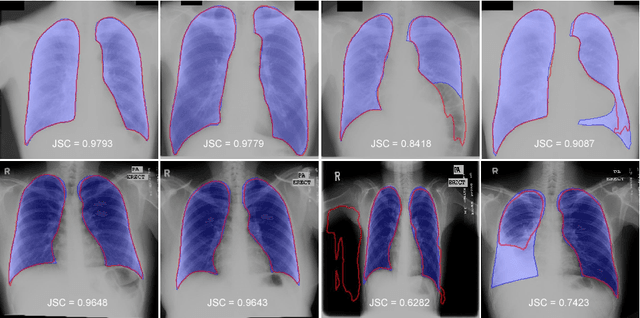

We introduce an accurate lung segmentation model for chest radiographs based on deep convolutional neural networks. Our model is based on atrous convolutional layers to increase the field-of-view of filters efficiently. To improve segmentation performances further, we also propose a multi-stage training strategy, network-wise training, which the current stage network is fed with both input images and the outputs from pre-stage network. It is shown that this strategy has an ability to reduce falsely predicted labels and produce smooth boundaries of lung fields. We evaluate the proposed model on a common benchmark dataset, JSRT, and achieve the state-of-the-art segmentation performances with much fewer model parameters.